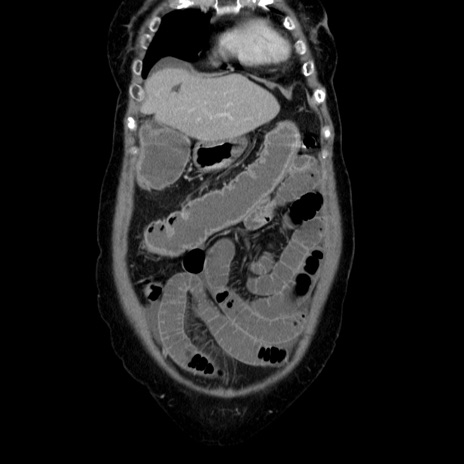

横断像

【症例】70歳代女性

【主訴】お腹が張る

【現病歴】1週間くらい前から腹部膨満の自覚あり。昨日夜から増悪したため、本日救急外来受診。

【身体所見】意識清明、BT 36.5℃、BP 165/106mmHg、HR 80bpm、SpO2 98%、腹部:膨満、軟、自発痛・圧痛なし、触診にて不快感あり、腸蠕動音:減弱

【データ】WBC 12600、CRP 1.04